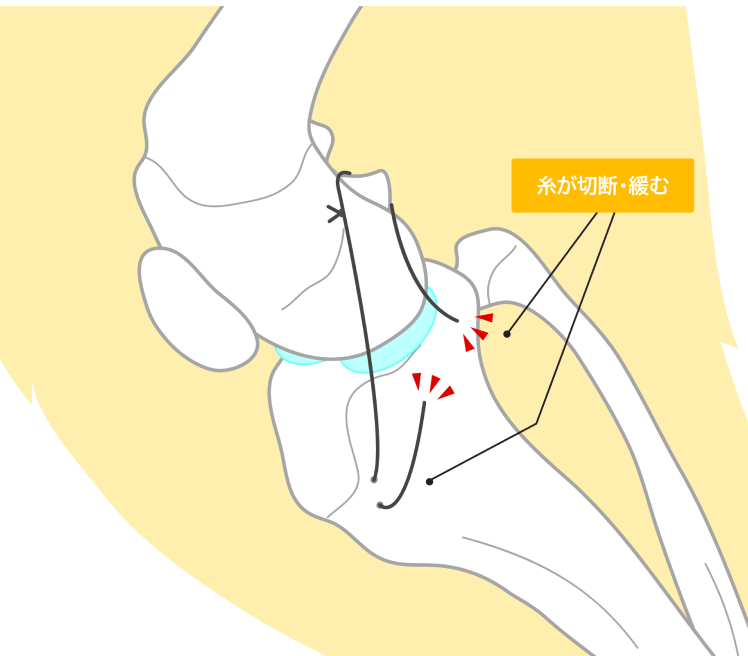

関節外制動法(Floの変法)

手術には主に2種類の方法があります。1つは、膝関節の外部に強力な人工素材や縫合糸を通して、切れてしまった前十字靭帯の役割を補うことで、脛骨が前方に滑らないようにします。これにより、膝を安定化させます。

デメリット

体重の重い大型犬では、かけた紐が緩みやすく関節外法による安定が不十分になることがあります。また、関節の可動域が制限されやすく、術後に症状が改善するまでの時間がTPLO法よりも長くなります。